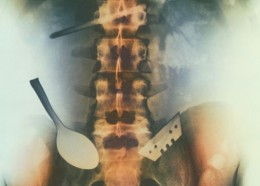

Чудни ренгенски снимки